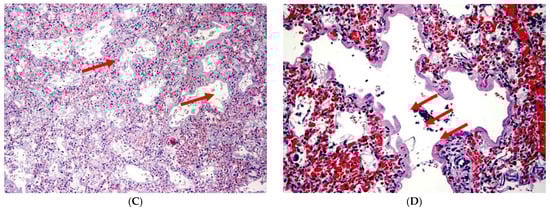

- Interstitial and endoalveolar hemorrhage with a diffuse or nodular pattern;

- Presence of endoalveolar hyaline membranes; (not necessary but possibly found)

- Accumulation of macrophages, siderophages, and hemosiderin as markers of previous bleeding; (not necessary, but possibly found);